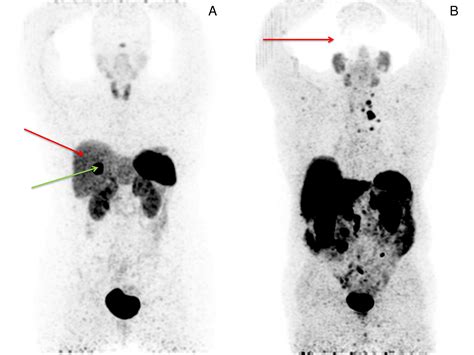

• Accurate Staging: It helps doctors determine how far a tumor has spread (metastasized) from its original site.

• Monitoring Progress: It can be used to assess how well a current treatment is working or to check for recurrence after treatment has been completed.